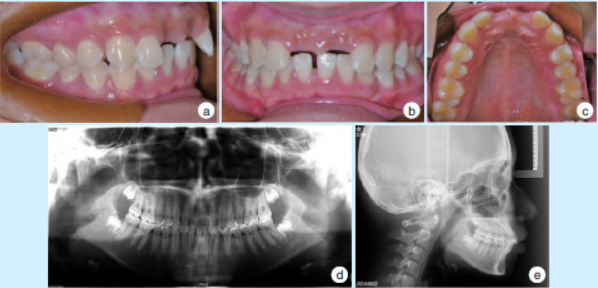

2.1 正畸治疗前(2016 年)

口内检查示:口腔卫生条件尚可,牙列式17⁃12,22⁃27,38⁃35,33⁃43,45⁃48,11、21 缺失,双侧磨牙中性关系,深覆盖,31、41牙间隙约2 mm,牙龈色形质良好(图1a~1c)。全景曲面断层片及头颅侧位片示:11、21 缺失,深覆,上前牙区牙槽骨高度未见明显异常(图1d、1e)。

图1 正畸治疗前患者口内照、全景曲面断层片及头颅侧位片(2016年)